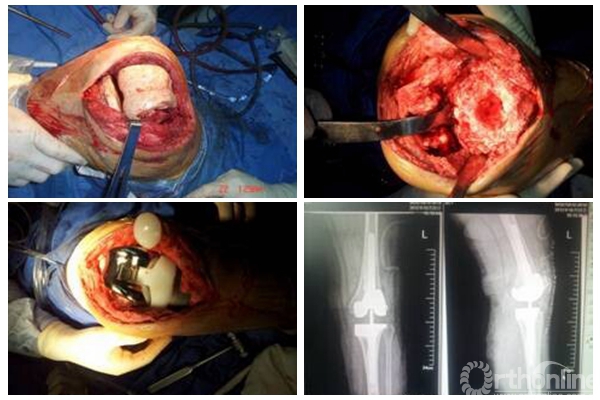

肿瘤型人工膝关节翻修技术

重视患者的术后随访,当复诊时聚乙烯内衬磨损到一定程度,而患者尚未出现明显临床症状前就进行内衬的更换,可以避免大翻修的数量,不仅减少了患者的痛苦,也节约了不少的费用。例如,对严重髋臼骨缺损患者,采用国际最新的CUP-CAGE技术,有效地使得患者的翻修假体生存时间延长。对膝关节置换感染患者,采用二期翻修技术,植入自制含抗生素骨水泥的SPACER,运用膝关节翻修假体,治愈了膝关节置换感染病例。